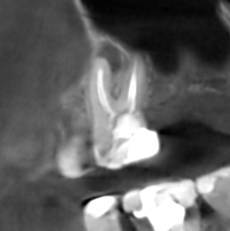

Александр В.В. Опубликовано 29 марта, 2023 Поделиться Опубликовано 29 марта, 2023 (изменено) Здравствуйте! Уже давно на шестом верхнем зубе есть гранулёма или киста размером 5-6 мм. Несколько лет назад пробовали класть кальций в каком-то виде, но, видимо, не помогло. Сейчас всё-таки решил перелечить этот канал, но эндодонтист сказал, что это только часть дела и надо делать все каналы. Кроме того, как я понял, проблема не в том канале, который запломбирован, а в том, который проходит рядом с ним и не был обнаружен и запломбирован. На этом снимке это верхний левый корень и в его правой части темное пятно - это вроде и есть тот ненайденный канал. Здесь видна гранулёма и запломбированный канал (корень слева). А здесь справа от запломбированного канала (левого корня), тот самый незапломбированный. Но у меня есть сомнения по поводу такого вывода, потому что в других каналах можно обнаружить более очевидные "темные каналы" в зависимости от среза. На этих снимках обращаю ваше внимание на правый канал. Если нужно, могу предоставить другие проекции, потому что имею диск с данными КЛКТ. Вопросы. 1. Действительно ли на снимке ненайденный канал на корне зуба с гранулёмой? 2. Возможно ли перелечивание одного канала с гранулёмой или кистой или нужно распломбировать сразу все каналы во всех корнях? 3. Если на снимке всё-таки ненайденный канал, то не кажется ли вам, что он прямой, а не изогнутый? Если прямой, его может обработать терапевт без использования микроскопа? Изменено 29 марта, 2023 пользователем Александр В.В. Ссылка на комментарий

Александр В.В. Опубликовано 16 декабря, 2023 Автор Поделиться Опубликовано 16 декабря, 2023 Здравствуйте! Провёл лечение этого зуба, а гранулёма и боли остались. Прошу совета. Рассказываю по порядку. 1. До перелечивания этого зуба (шестнадцатый) были постоянные воспаления десны из-за разрушенной коронки зуба и неровных краёв пломбы в поддесневой части со стороны отсутствующего соседнего зуба. Также были боли при прикосновении пальцем десны в проекции корней зуба со стороны щеки, то есть, примерно там, где находится гранулёма. При этом припухлости этой области я не замечал. 2. На первом этапе лечения были рассверлены каналы, в том числе и ранее не найденный, и на 7 дней заложен препарат для растворения остатков пломбировочного материала. Также была установлена временная пломба. Уже после первого посещения я заметил, что ушла боль при прикосновении пальцем проекции корней. Но 2-3 дня периодически происходило выделение бурой жидкости из носа в виде капель при наклоне головы. Зуб не болел, ничего не опухало. 3. На втором этапе были удалены остатки пломбировочного материала из корней, заложен препарат кальция для «лечения» и снова установлена временная пломба. Точно не знаю, для чего применяется кальций. То ли как антисептическое средство, то ли для восстановления костной ткани. Опять несколько дней наблюдалось выделение жидкости из носа. Болей не было три недели ни в области проекции корней, ни десны со стороны отсутствующего зуба, а потом опять начала болеть десна скорее всего из-за разрушения временной пломбы. С кальцием ходил 30 дней. 4. На третьем этапе были запломбированы все каналы, установлен стекловолоконный штифт и восстановлена коронка зуба с помощью пломбировочного материала, но при этом зуб был выведен из прикуса. Стоматолог предупредил, что зуб может болеть 2 недели, как это бывает после пломбирования. На этот раз никаких выделений из носа не было. Болей или опухания тоже не было. Но примерно через 8 дней опять начала болеть десна, как со стороны отсутствующего зуба, так и в проекции корней, причём, мне кажется, что даже сильнее, чем раньше. Возможно, это связано с тем, что я начал пытаться жевать этим зубом и более смело пользоваться зубной щёткой. Новые снимки зуба показали, что гранулёма осталась на своём месте. Вопросы. 1. Нормально ли то, что гранулёма осталась, несмотря на проведённое лечение? 2. На снимке потемнение десны справа от зуба – это воспаление? В чём может быть его причина? 3. Что появилось в пазухах? На снимках, сделанных год назад, этого не было. 4. Почему проходили боли на первых этапах лечения и появились снова после его окончания? 5. Что делать дальше? Ждать, что само пройдёт или принимать какие-то меры? Систематически таблетки не пил. Только однократный приём НПВС после каждого посещения стоматолога. Сейчас провожу полоскание зуба различными препаратами и мажу разными мазями и гелями для дёсен. Ссылка на комментарий